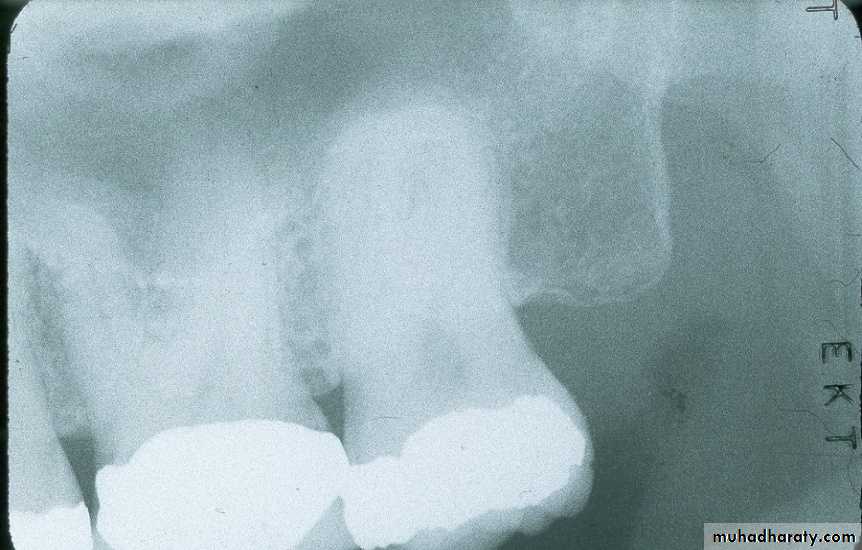

Maxillary Incisor

centered on contact between central and lateral incisorsfilm placed far back in patient’s mouth

Maxillary Canine

film centered on caninefilm placed against the opposite side of the arch, far away from the canine